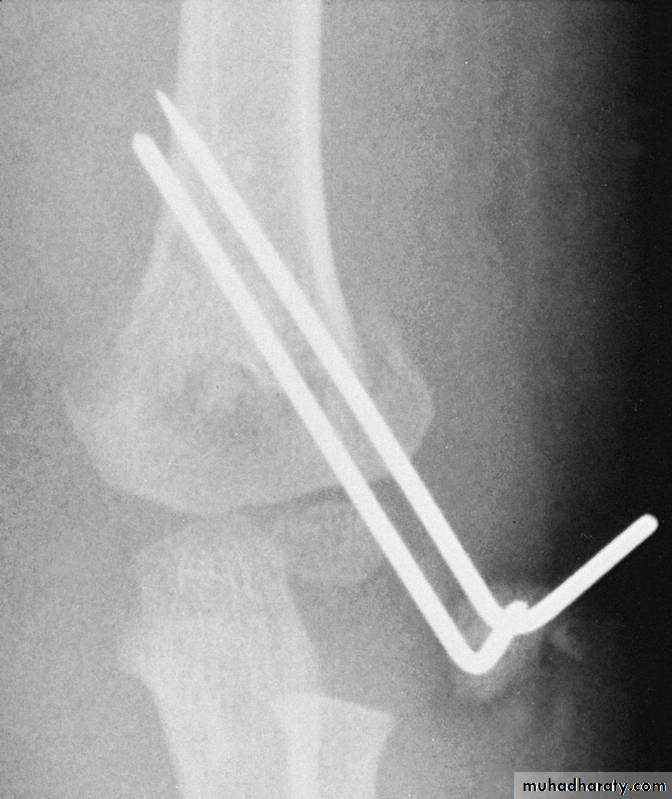

With Type II fractures, if

there is any concern about

vascular compromise

or fracture stability

due to the severe swelling,

then secure the fragments

with percutaneous pins,

so that the extremity can be

immobilized at 90 degrees.

Medial-lateral

pins

How can the danger of ulnar nerve

injury be minimized?By

making an incision

directly over the

medial epicondyle,

to locate the

medial epicondyleby direct vision.

Then, insert the medial pin by direct vision

into the center of the medial epicondyle.while the ulnar nerve

is

retracted posteriorly.